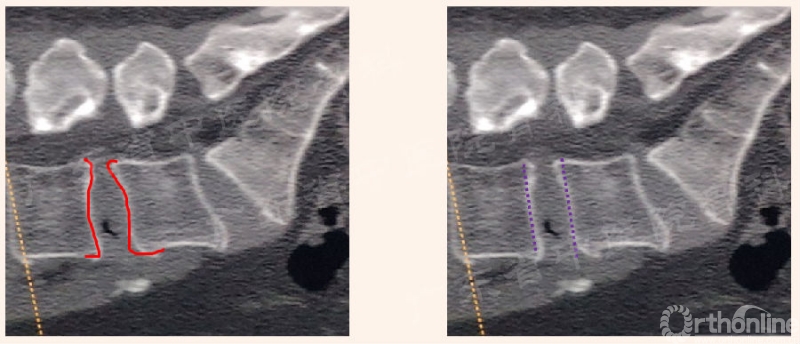

2. 椎板切除术

第1管:下关节突

关键:

显露解剖结构

定位关节突

部分可见黄韧带

第2管/半管:椎板及外侧峡部

上关节突尖

显露黄韧带起点

第3半管(选择性):椎板

骨性空间扩大

显露黄韧带